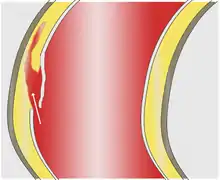

As with all other arteries, the aorta is made up of three layers, the intima, the media, and the adventitia. The intima is in direct contact with the blood inside the vessel, and mainly consists of a layer of endothelial cells on a basement membrane; the media contains connective and muscle tissue, and the vessel is protected on the outside by the adventitia, comprising connective tissue.[16]

In an aortic dissection, blood penetrates the intima and enters the media layer. The high pressure rips the tissue of the media apart along the laminated plane splitting the inner two-thirds and the outer one-third of the media apart.[17] This can propagate along the length of the aorta for a variable distance forward or backwards. Dissections that propagate towards the iliac bifurcation (with the flow of blood) are called anterograde dissections and those that propagate towards the aortic root (opposite of the flow of blood) are called retrograde dissections. The initial tear is usually within 100 mm of the aortic valve, so a retrograde dissection can easily compromise the pericardium leading to a hemopericardium. Anterograde dissections may propagate all the way to the iliac bifurcation of the aorta, rupture the aortic wall, or recanalize into the intravascular lumen leading to a double-barrel aorta. The double-barrel aorta relieves the pressure of blood flow and reduces the risk of rupture. Rupture leads to hemorrhaging into a body cavity, and prognosis depends on the area of rupture. Retroperitoneal and pericardial ruptures are both possible.

The initiating event in an aortic dissection is a tear in the intimal lining of the aorta. Due to the high pressures in the aorta, blood enters the media at the point of the tear. The force of the blood entering the media causes the tear to extend. It may extend proximally (closer to the heart) or distally (away from the heart) or both. The blood travels through the media, creating a false lumen (the true lumen is the normal conduit of blood in the aorta). Separating the false lumen from the true lumen is a layer of intimal tissue known as the intimal flap.

The vast majority of aortic dissections originate with an intimal tear in either the ascending aorta (65%), the aortic arch (10%), or just distal to the ligamentum arteriosum in the descending thoracic aorta (20%).

As blood flows down the false lumen, it may cause secondary tears in the intima. Through these secondary tears, the blood can re-enter the true lumen.